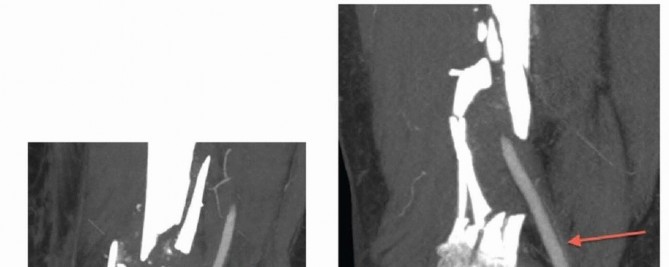

### FIG 3 • A. Patient with a grade IIIA open distal femur with extruded fragment; the “extension” of the femoral condyles is outlined. B. Patient with a distal femur fracture with intercondylar extension showing the subtle rotational deformities of the individual condyles. C. The muscle forces are shown on the distal femur, as is the femoral artery and vein entering the canal of Hunter (arrow). The adductor magnus inserts on the adductor tubercle, leading to a varus deformity of the distal segment. D. A lateral image of the same patient with the popliteal artery and tibial nerve drawn in to show the relative proximity to the fracture ends. 468

### FIG 4 • A,B. Coronal and sagittal CT angiography images showing intact femoral artery in a severely comminuted distal femur fracture (red arrows). Dedicated knee films should always be obtained in the assessment of distal femur fractures. Additionally, the entire femur, to include the hip and knee, should be imaged to look for possible extension and associated injuries and to allow for preoperative planning ( FIG 5). In cases of severe comminution, radiographs of the contralateral knee can aid in preoperative planning as well. A dedicated CT scan is an important adjunct to the preoperative planning when there is articular involvement ( FIG 6). Generally, extra-articular distal femur fractures do not require a CT scan. However, it has been shown that coronal fractures may be missed on plain films, and thus there is a low threshold for obtaining a CT scan for fractures of the distal femur. 11 If the fracture pattern warrants a temporary bridging external fixator, it is best to obtain the CT scan after placement of such a fixator for better definition. Coronal and sagittal reconstructions should be requested. Three-dimensional images can be created from most CT scans. This can also aid in the preoperative planning ( FIG 7A,B). Subtle sagittal plane rotational malalignment between condyles can be assessed ( FIG 7C). If associated soft tissue injury is suspected, such as ligamentous tears or tendon ruptures, then magnetic resonance imaging (MRI) may be indicated. Routine use of MRI, however, is not needed. ## DIFFERENTIAL DIAGNOSIS Proximal tibia fracture Femoral shaft fracture Septic knee Patella fracture Anterior cruciate ligament rupture Knee dislocation ## NONOPERATIVE MANAGEMENT There are few relative indications for nonoperative management of distal femur fractures: Poor overall medical condition Patient has severe comorbidities and is too sick for surgery. Patient has extremely poor bone stock. Spinal cord injury (paraplegia or quadriplegia) Some special situations may warrant nonoperative care on case-by-case basis. Nondisplaced or minimally displaced fracture Select gunshot wounds with incomplete fractures Extra-articular and stable Unreconstructable Lack of experience by the available surgeon or lack of equipment or appropriate facility to adequately treat the injury. Transfer is indicated in these situations; otherwise, nonoperative treatment may be the only option. There are several methods for nonoperative treatment. Skeletal traction Cast bracing Knee immobilizer Long-leg cast There are acceptable limits for nonoperative management: Seven degrees of varus or valgus Ten degrees of anterior or posterior angulation. A flexion deformity is less well tolerated than an extension deformity. Up to 1 to 1.5 cm of shortening Two to 3 mm of step-off at the joint surface 469